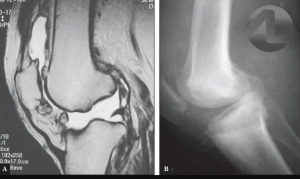

A consulta com o médico é importante para avaliar a gravidade junto à história contada pelo paciente e exame físico bem realizado. Se necessário, poderá ser necessário alguns exames de imagem como a ressonancia magnética para melhor diagnóstico do caso.

Quando possível, a complementação com os Exames de Imagem, como a Ressonância Magnética, para analisar o volume de cartilagem que foi degradado será solicitada. A Radiografia também é extremamente importante no diagnóstico e no tratamento em caso de artrose.